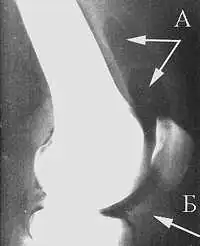

Рентгенологическая семиотика остеоартроза складывается из признаков, отражающих дистрофические изменения в суставных хрящах (сужение суставной щели) и в костной ткани (уплощение и деформация суставных поверхностей, кистовидные образования), нестабильность суставов (подвывихи, искривления оси конечностей), реактивные компенсаторно-приспособительные процессы (краевые костные разрастания, субхондральный остеосклероз).

Ранним рентгенологическим симптомом являются краевые костные разрастания — остеофиты — следствие активной пролиферации периферических отделов суставного хряща. Они проявляются вначале заострением краёв суставных поверхностей, а затем, нарастая, образуют массивные костные шипы и губы. Краевые остеофиты, как правило, раньше обнаруживаются со стороны суставных впадин.

Сужение суставной щели свидетельствует о значительных изменениях суставных хрящей. Суставная щель может стать клиновидной, суживаясь с одной стороны и нередко расширяясь при этом с противоположной, что указывает на недостаточность связочного аппарата и нестабильность сустава.

- Остеоартроз на I стадии характеризуется главным образом краевыми костными разрастаниями при незначительном сужении суставной щели.

- На II стадии она сужена более отчётливо, возникает субхондральный остеосклероз.

- Резкое сужение суставной щели на III стадии сопровождается уплощением суставных поверхностей и развитием кистовидных образований.